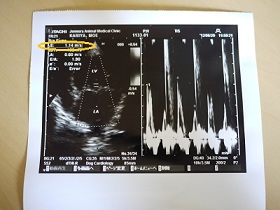

念の為、波計だけ撮ってもらいました。

一週間前の肺水腫と診断された日は1.5m/sだったのに

今日は1.14m/sと 心臓への負担がかなり減っていました。

以前にこの数値になった時は、

経過観察も1ヶ月単位でいいよ。って言われた値です。